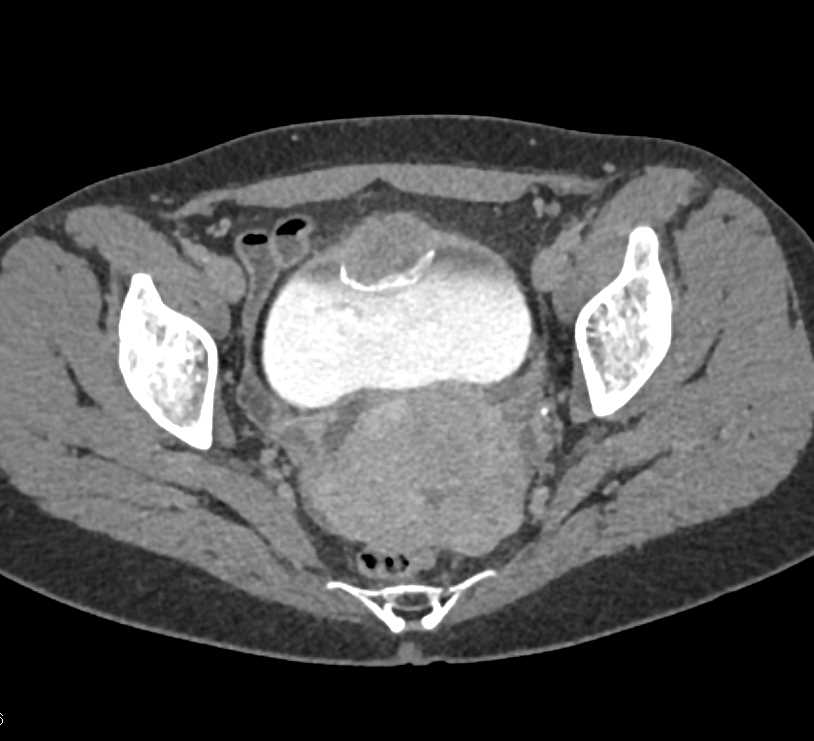

Urachal Carcinoma of the Bladder